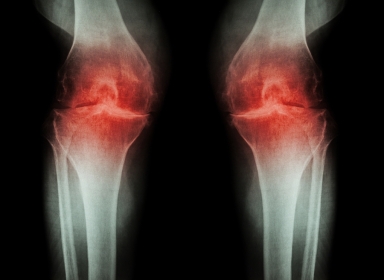

Il piede è forse ...Artrosi del ginocchio

05/01/2017

L'artrosi del ginocchio (anche detta gonoartrosi) è una malattia degenerativa dell'articolazione, che a poco a poco crea un'alterazione...Problemi circolatori agli arti inferiori